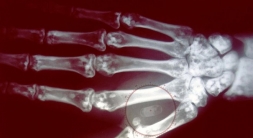

A pequena protuberância no dorso da mão de Dave Williams tem o tamanho de um grão de arroz e fica entre o polegar e o indicador. É quase imperceptível, mas quando ele a usa para abrir a porta de sua casa, vira o centro das atenções.

Este engenheiro de software britânico, tem um microchip implantado na mão, um circuito eletrônico que funciona com tecnologia sem fio.